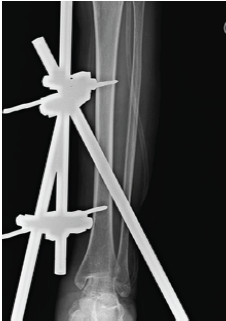

Tibial Osteomyelitis due to Burkholderia pseudomallei in a Non-diabetic Patient: A Case Report

Zobiakhlui Chhakchhuak , Lalnghakliana Hmar ………………………………p.238-241